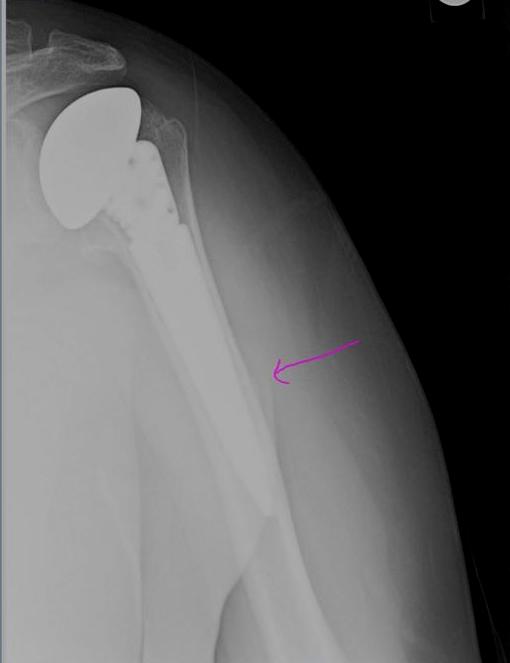

How to read Xray after the TSA (total shoulder arthroplasty) Sumer's Radiology Blog History Of Shoulder Replacement Icd 10  This site is dedicated exclusively to helping. It is found in the. The code is valid during the current. Web icd 10 code for presence of right artificial shoulder joint. Web  since the end of the 19th century, when the first shoulder prosthesis was implanted, an impressive. Web z96.611 is a billable diagnosis code used to specify a medical diagnosis. History Of Shoulder Replacement Icd 10.